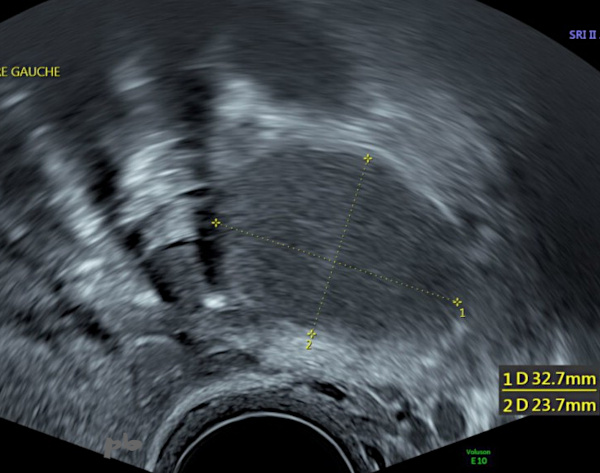

14- Diagnostic différentiel – Corps jaune kystique

Image hypoéchogène homogène et régulière.

Persistance sur 2 échographies de suivi sur une période de 9 mois : faux diagnostic d’endométriome.

Pas d’IRM.

Anapath : corps jaune kystique.